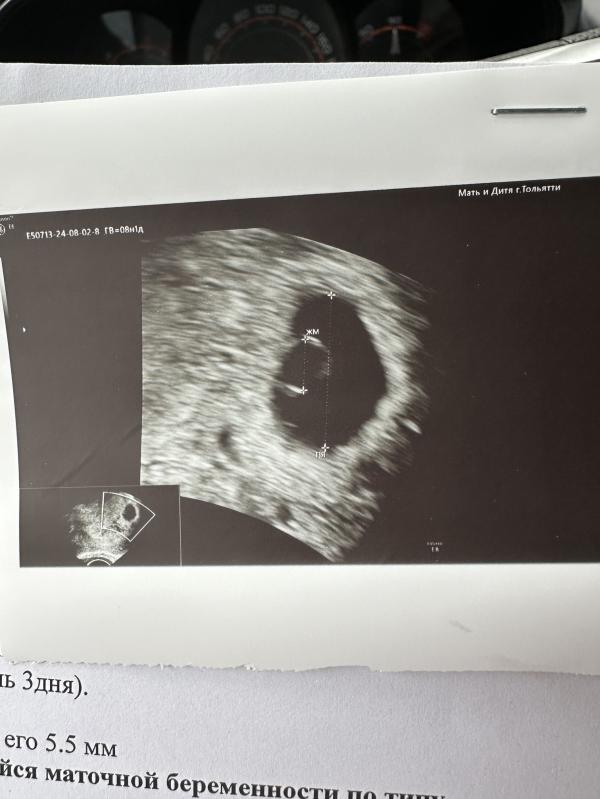

Ну всё печально девочки 🥲🥲🥲 так эмбрион не появился на 38дпп, плодное яйцо как было на той неделе 16 мм так и есть, желточный мешочек увеличился правда. Были по стенкам какие то полосочки но говорит по срокам не подходят такие утолщения на стенках жм. Сказала ре отменить поддержку попробуем отменструировать, если нет то на аборт(((